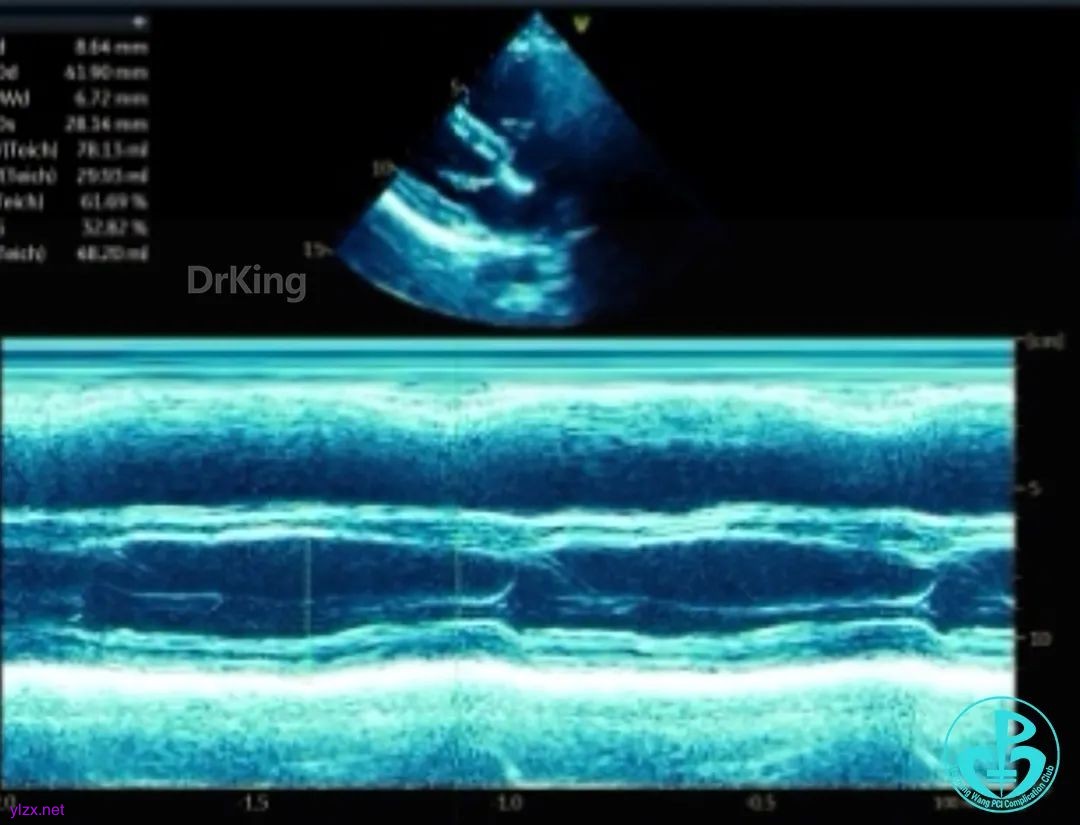

超声检查

房间隔中部有回声中断,测ASD大小:8×8×9mm,CDFI探及左向右分流,距主动脉根部0mm,距二尖瓣环10mm,距房顶14mm,距上腔静脉13mm,距下腔静脉11mm。

心脏彩超提示:先天性心脏病:房间隔缺(继发孔型)。右室稍增大。左心室收缩及舒张功能正常。右心室收缩功能正常。下腔静脉瓣冗长。